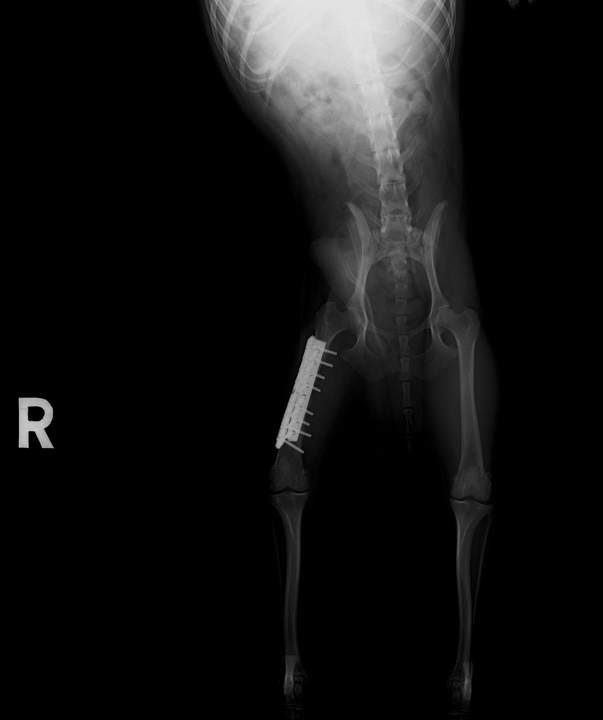

この子も他院の紹介です。アクシデントにより、大腿骨(太もも)骨折で来院されました。昨年、手術を行いましたが、元気な子なのでプレート自体が折れてしまいました。

再手術によりプレート(ダブル)が安定し、今では普通にしている様子。チタンを使用していますが、骨折端の骨吸収がないかどうかの定期チェックです。

すでに半年が経ち、問題なさそうです。元気な子なので、普通に歩けることが幸せそうです。よかったね、ルフィちゃん!

手術で成功しても、その後の安静が大切です。

これは、性格だけではなく、骨折部位にもよります。

ギプス固定が効かない関節や骨に関しては、注意が必要です。